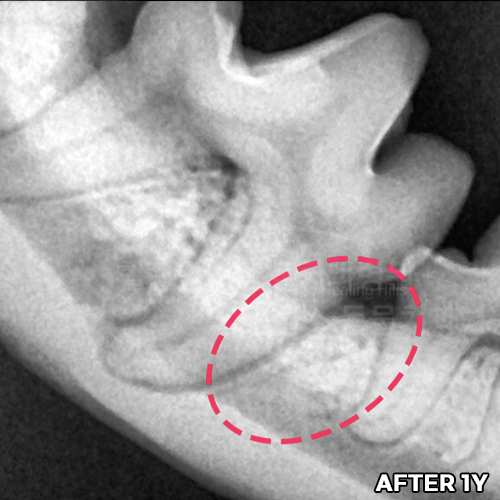

[사라진 강아지 턱떨림 / 재생된 턱뼈]

[강아지잇몸뼈 재생치료 하고 재생된 자기 잇몸뼈]